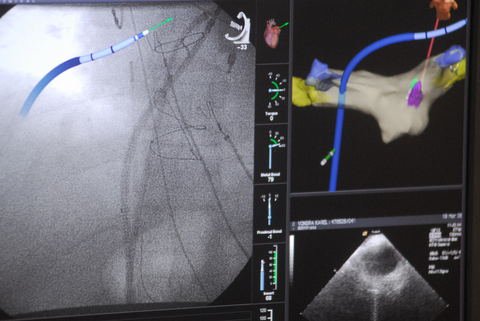

Live Cases